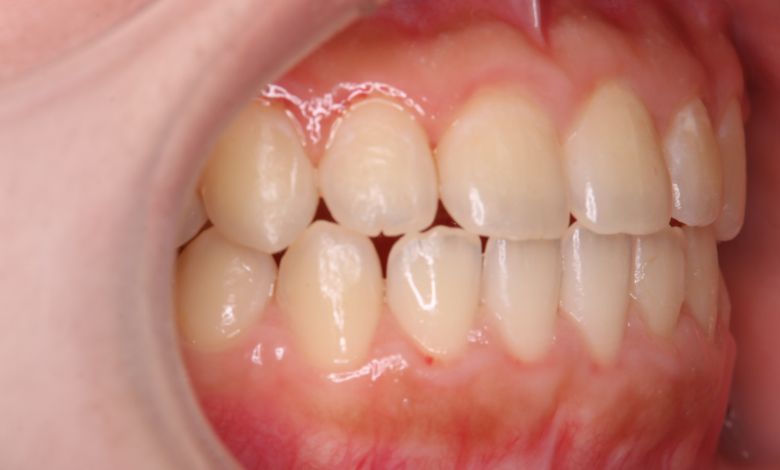

叢生が解消され、歯列全体にわたり滑らかで調和のとれた配列が得られています

上下の前歯の重なりが解消され、歯軸の傾きも整いました。咬合関係も安定しています

精密検査の結果、当院では抜歯を行わず、歯列弓の拡大によってスペースを確保し、非抜歯での矯正治療を選択しました。歯列の叢生(ガタガタ)は解消され、機能的かつ審美的に優れた咬合が得られました。